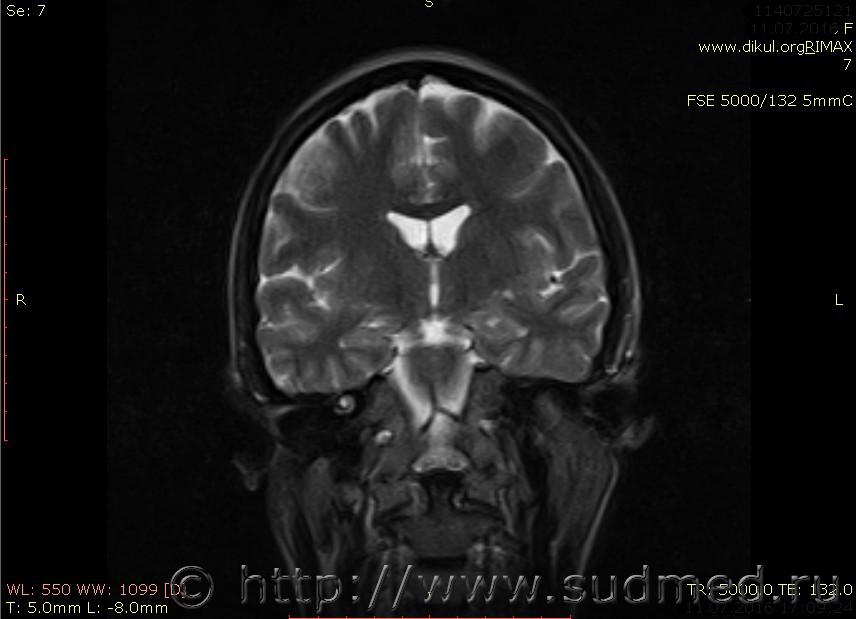

МРТ головного мозга показало: МР-данных за наличие очаговых изменений в веществе головного мозга на момент исследования не выявлено. МР-признаки нарушения соотношения в атланто-осевом суставе. Определяется ассиметрия положения зубовидного отростка С2 относительно боковых масс С1(справа 6,5; слева 4 мм.)

Сама по себе эта информация даёт основания подозревать вывих первого шейного позвонка, но однозначно не свидетельствует о наличии вывиха. Нужно смотреть на снимках наличие реакции со стороны мягких тканей, в т.ч. связочного аппарата, нужно анализировать особенности неврологической патологии, её динамику и проч.

Запрошен электронный вариант снимков из учреждения, где делалось МРТ. Т.к. с самого снимка делать копии не получается,очень мелкие кадры. Завтра попробую вставить в сообщение. (Но СМЭ снимок не смотрел, смотрел только мед.карту, в которой находилось описание МРТ).

Посмотрите пожалуйста снимки, надеюсь на них видны позвонки С1,С2?

Прошу прощения, попробую снова прикрепить файлы. Данные учреждения и пациента убраны.